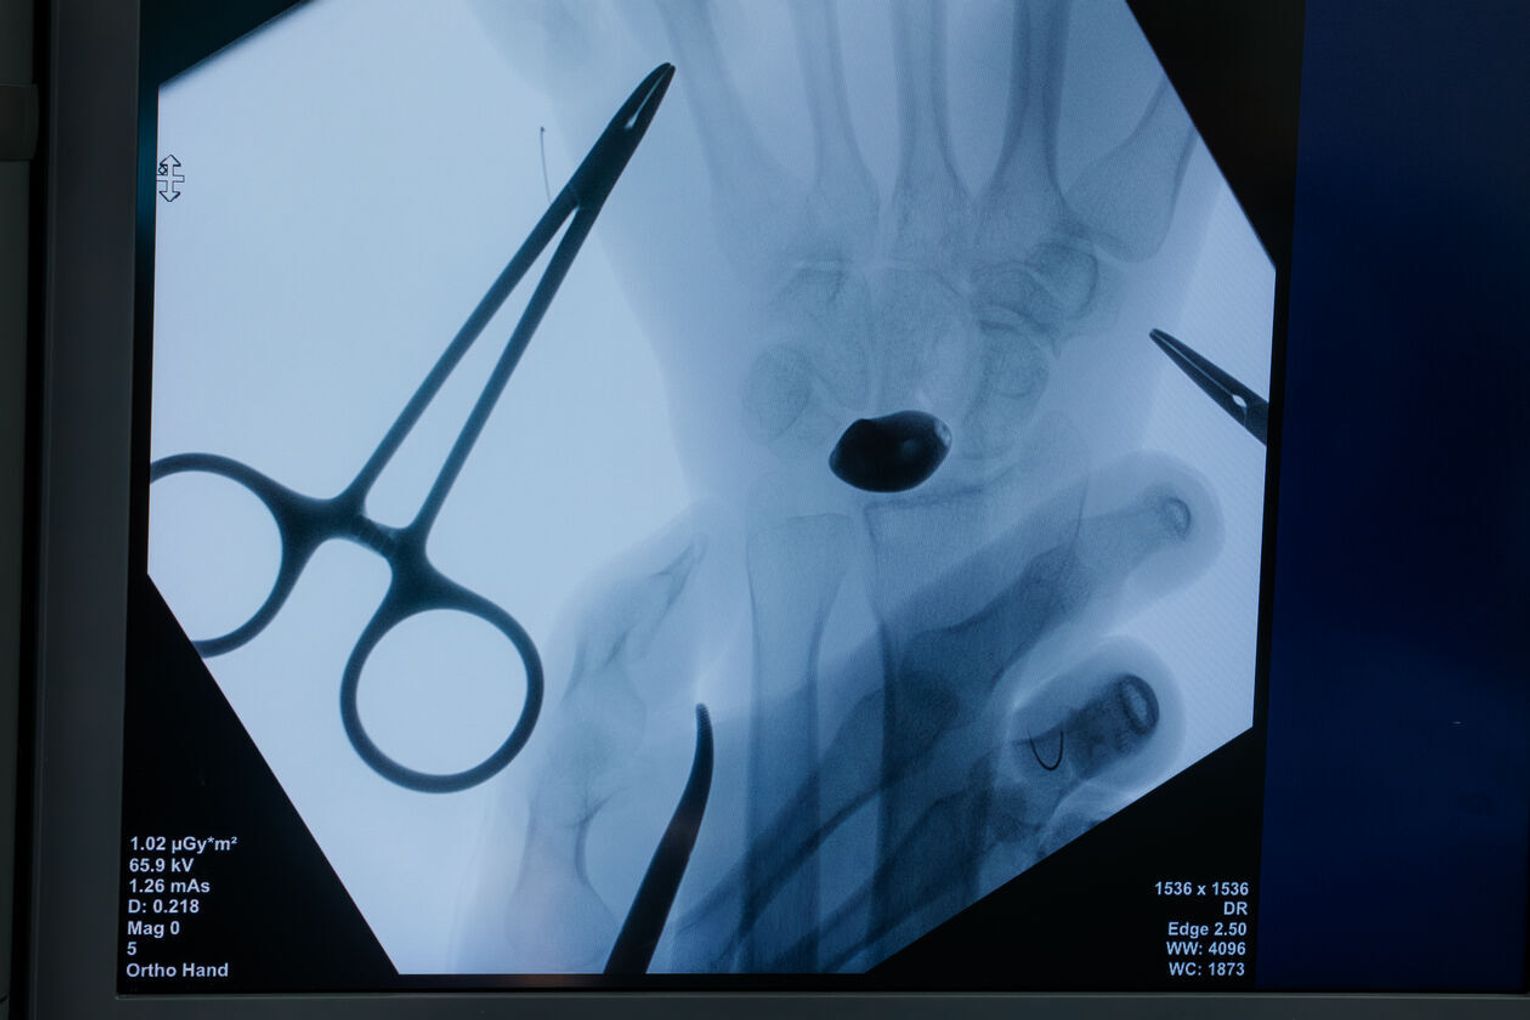

Przygotowania do operacji trwały rok. Lekarze wykonali cyfrowy model nadgarstka, na podstawie którego powstał implant z biokompatybilnego stopu tytanu. Powierzchnie odpowiedzialne za ruch i kontakt ze stawem wygładzono lub pokryto powłoką diamentopodobną, aby zminimalizować tarcie.

Zabieg przeprowadził zespół pod kierownictwem dr. n. med. Piotra Piecha.

– O sukcesie decyduje nie tylko sam implant, lecz także chirurgiczna precyzja i odpowiednia plastyka tkanek miękkich – podkreśla ortopeda.